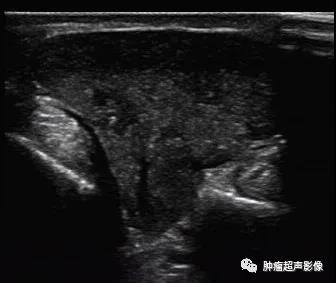

病理证实的血管平滑肌瘤,男42,手背、单发的疼痛结节,超声表现为皮下边界清的蘑菇形(肿块较大,各个方向生长压力不同),低回声内见条状无回声,包膜完整,血流稍丰富,符合血管平滑肌瘤表现。